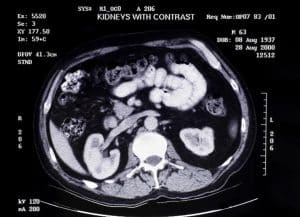

Computed Tomography (CT) Scan: Appears to utilize X-ray and computers to take a picture of the kidneys and tissues in another plane. Offers clear images and can be used in diagnosing kidney stones, tumors, and constituents of the urinary system obstructs. CT urography is a specific type of CT scan that focuses particularly on the system of the urinary tract.

Computed Tomography (CT) Scan

Fasting for a few hours before the scan. Hydration may be encouraged to help protect the kidneys. The patient lies on a motorized table that slides into the CT scanner. Intravenous contrast may be given to enhance image quality. Oral contrast may be used in some cases. The scanner rotates around the patient, taking multiple X-ray images that are then reconstructed into cross-sectional slices.

Computed Tomography (CT):

Advantages: Produces good spatial and contrast detail; helpful for attempting to assess the presence of renal abnormalities and urinary tract obstruction of over 5mm in size as well as tumor and stones assessment and renal artery patency.

Limitations: It uses ionizing radiation, and the contrast agents could be contraindicated in patients who have renal problems.